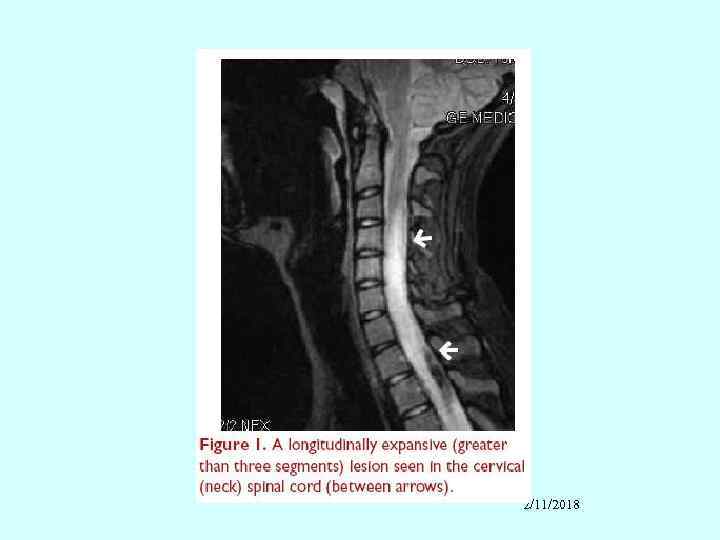

Other neural system features • • • Peripheral neuropathy Cranial neuropathy – usually affects eyes Transverse myelitis Neuromyelitis optica Myelopathy Eye – cytoid bodies (vasculitis of retinal capillaries) _______________ Infection always must be excluded!!!!!! 2/11/2018

2/11/2018